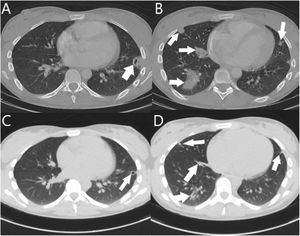

A 19-year-old woman who, after treatment for acute tonsillitis, went to A&E with continuous pain in the pubic area. A chest X-ray was performed that revealed pseudonodular condensations (Fig. 1A), complementing the study with computed tomography (CT), which confirmed the presence of septic emboli (Fig. 1B and C), for which the patient was admitted. An ultrasound of the neck ruled out thrombophlebitis of the jugular vein. A blood culture was obtained and intravenous broad-spectrum antibiotic therapy with meropenem and linezolid (1 g/8 h and 600 mg/12 h, respectively) was prescribed. A pelvic CT confirmed the presence of pubic symphysitis (osteitis pubis) with abscessification (Fig. 2). Surgical cleaning with debridement was performed, and two samples were sent for culture.

In the Gram stain, 10–25 leukocytes/field were observed in the absence of microorganisms. Samples were inoculated in Thioglycollate® enrichment broth, as well as on different agars (chocolate, CNA and TSA with 5% sheep blood, MacConkey, Sabouraud with chloramphenicol, Brucella, BBE with amikacin and kanamycin-vancomycin blood). After 96 h of incubation, no growth was observed in the cultures. In follow-up CT scans, an involution of the pulmonary septic emboli was observed (Fig. 3), as well as disappearance of the pubic collection.